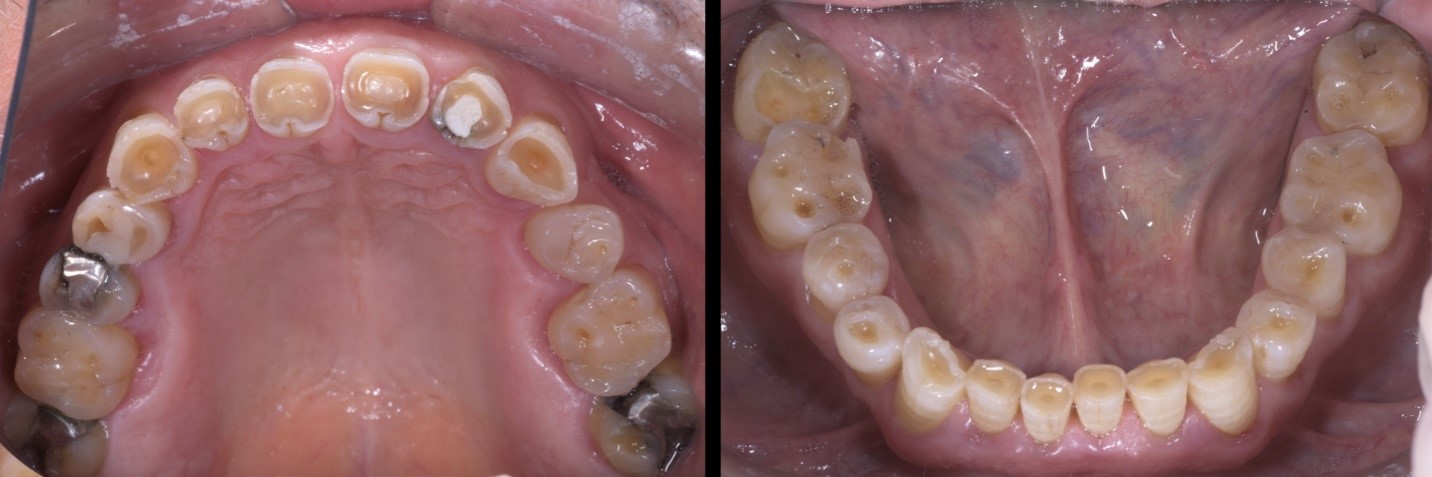

Fig. 2a e 2b

Dopo un attento studio del caso, si opta per una riabilitazione completa con rialzo della dimensione verticale di occlusione. Il rialzo calibrato della DVO viene testato mediante mock-up per un periodo di 2 mesi.